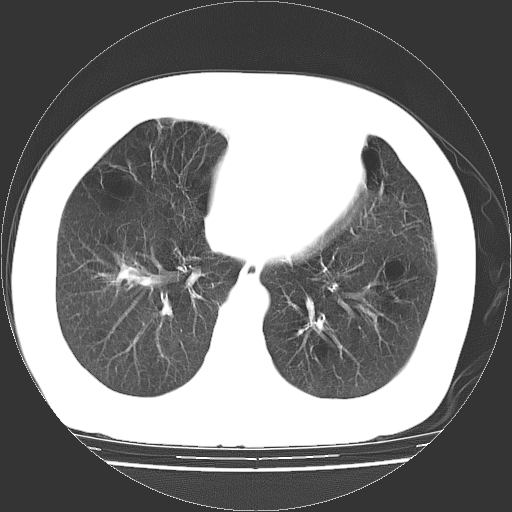

标题: CT13141:女,70岁,咳嗽、胸闷半个月。 [打印本页]

标题: CT13141:女,70岁,咳嗽、胸闷半个月。

女,70岁,咳嗽、胸闷半个月。纵隔窗未见异常,未上传。

慢支炎、肺气肿征,双肺多发肺大泡

小叶中心型肺气肿并多个肺大泡形成。

小叶中心性肺气肿及间隔旁肺气肿.(多与吸烟有关)